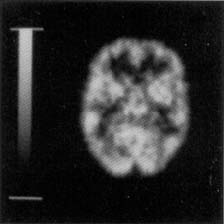

Hoffman 2-D Brain Phantom™

For Brain PET and SPECT studies

- Thickness differences between ventricle, gray and white matter simulate the radioactivity distribution in a single slice of a brain ECT study

- Normal gray-matter:white-matter:ventricle radioactivity ratio is 4:1:0 (simulated by partial volume effect)

- Evaluation of acquisition and reconstruction methods for brain PET and SPECT studies